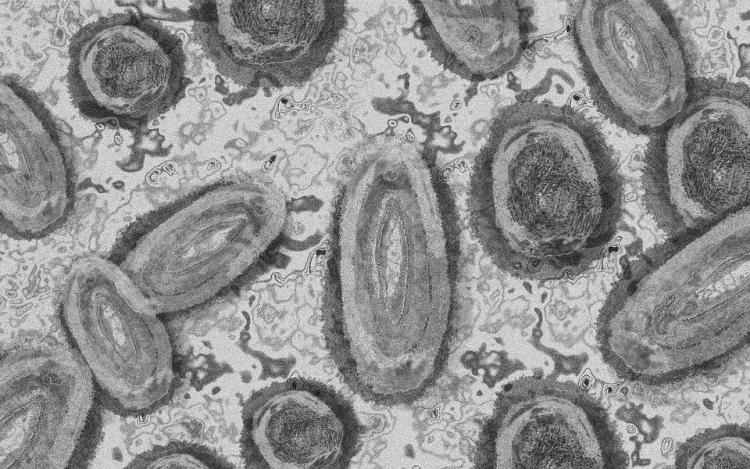

Újabb hét magyarnál igazolták a majomhimlőt

Újabb hét embernél igazolták a majomhimlőfertőzést a Nemzeti Népegészségügyi Központ (NNK) veszélyes kórokozókkal foglalkozó laboratóriumában; ezzel 19-re nőtt az igazolt majomhimlő fertőzöttek száma Magyarországon

- tájékoztatta az NNK csütörtökön az MTI-t.